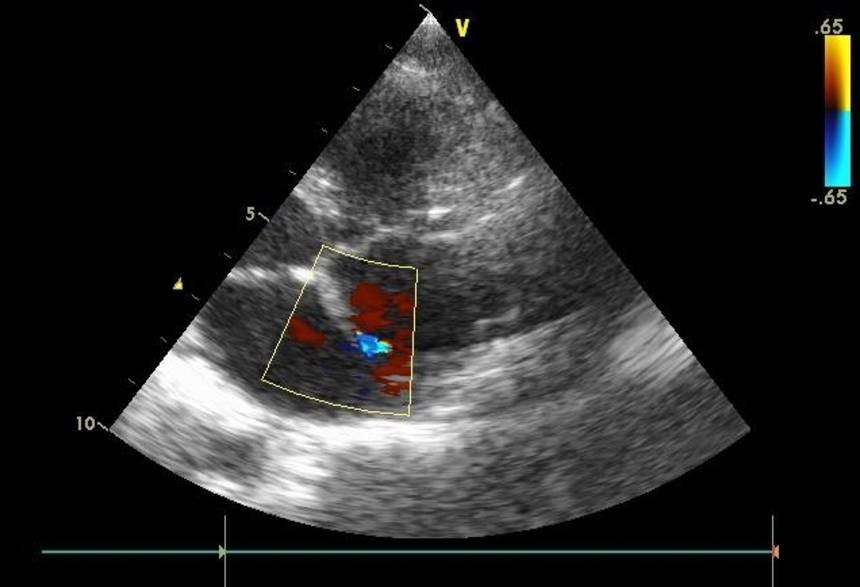

Врожденные пороки сердца диагностирует неонатолог (порок сердца у новорожденных), семейный врач, педиатр (порок сердца у детей), терапевт (врожденный порок сердца у взрослых), детский кардиолог, кардиолог, специалист по ультразвуковой диагностике, эндоваскулярный хирург, кардиохирург. Самый доступный, безопасный и при этом очень информативный инструментальный метод диагностики – ЭхоКГ с допплерографией. Для диагностики сложных врожденных пороков сердца применяют рентген контрастное исследование (вентрикулографию, ангиографию), КТ и МРТ, в том числе с контрастированием.

Порок сердца диагностирует семейный врач, педиатр, неонатолог, терапевт, кардиолог, кардиоревматолог, детский кардиолог, ревматолог, кардиохирург, эндоваскулярный хирург. Диагноз устанавливают на основании опроса, прослушивания сердца (каждый порок имеет характерный сердечный шум) и легких, ЭКГ, ультразвукового исследования сердца (ЭхоКГ) с допплерографией, записи шумов в сердце (фонокардиография), рентгенэндоваскулярного исследования сердца и сосудов (ангиография, вентрикулография, коронарография), рентгенографии сердца и легких, компьютерной томографии (КТ), магнитно-резонансной томографии (МРТ), пр.

Основным способом выявления патологии у ребенка является УЗИ сердца. Альтернативное название манипуляции – ЭХО-кардиография. Данная процедура абсолютно безболезненна и безопасна, поэтому является методикой выбора при диагностике многих врожденных патологий сердца. Для того чтобы увеличить информативность исследования, необходимо использовать современные аппараты УЗИ, а прием должны вести опытные специалисты, которые способны заметить даже небольшие нарушения гемодинамики. Такой подход позволяет обеспечить достоверную диагностику патологий даже у самых маленьких пациентов.